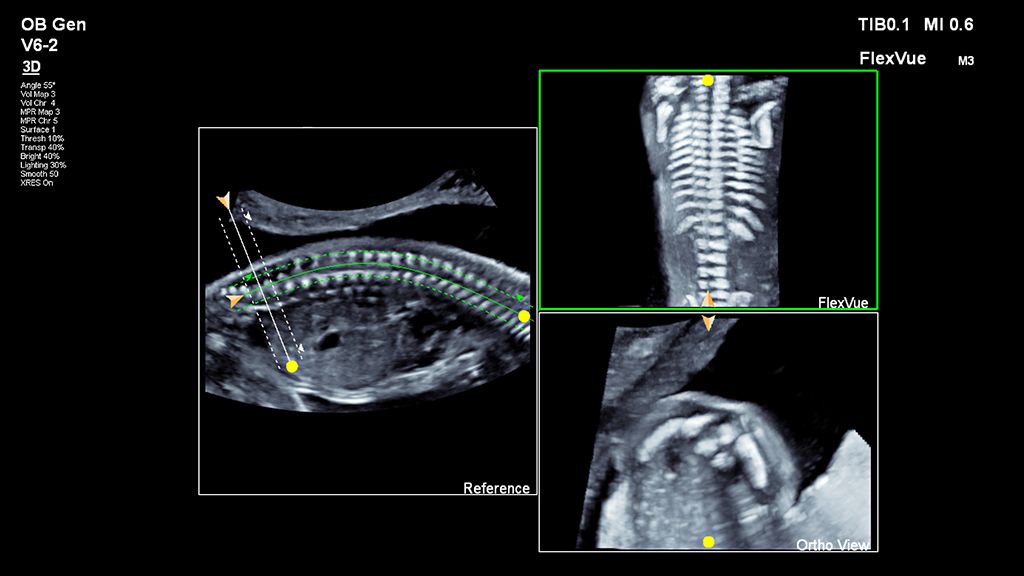

Demonstrated results using FlexVue

It (FlexVue) takes all of the complications out of MPR and manipulation of a surface-rendered volume. By deploying a straight line or a curved trace or continuous trace, we can take a curved image, flatten it out and make it a single planar image.